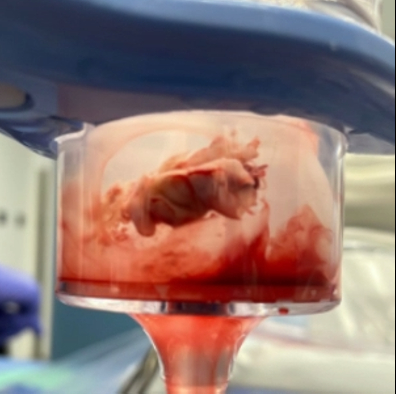

A 36-year-old female with a past medical history of depression, intravenous heroin use, and substance-induced mood disorder presented with altered mental status and respiratory distress. She was found to have methicillin-sensitive staphylococcus aureus (MSSA) bacteremia, a gluteal abscess, multiple septic pulmonary emboli, and a left-sided empyema. She was started on broad-spectrum antibiotics that were narrowed to cefazolin. Her gluteal abscess was drained, and a left-sided chest tube was placed with pleural cultures growing MSSA. TTE demonstrated a mass on the eustachian valve. Subsequent transesophageal echocardiography (TEE) demonstrated two echogenic masses adherent to the eustachian valve, one measuring 17 by 9 millimeters and one measuring 15 by 8 millimeters, consistent with eustachian valve endocarditis. Despite appropriate antibiotic therapy, she continued to have intermittent fevers with persistently positive blood cultures. The patient underwent TEE-guided extraction of the eustachian valve vegetation using the AngioVac aspiration system. TEE at the end of the case demonstrated complete removal of her eustachian valve masses. Blood cultures cleared post-procedure, and she was eventually discharged to acute rehabilitation.

In cases of eustachian valve endocarditis refractory to appropriate antibiotic therapy, the AngioVac aspiration system offers an option for percutaneous extraction of eustachian valve vegetations.